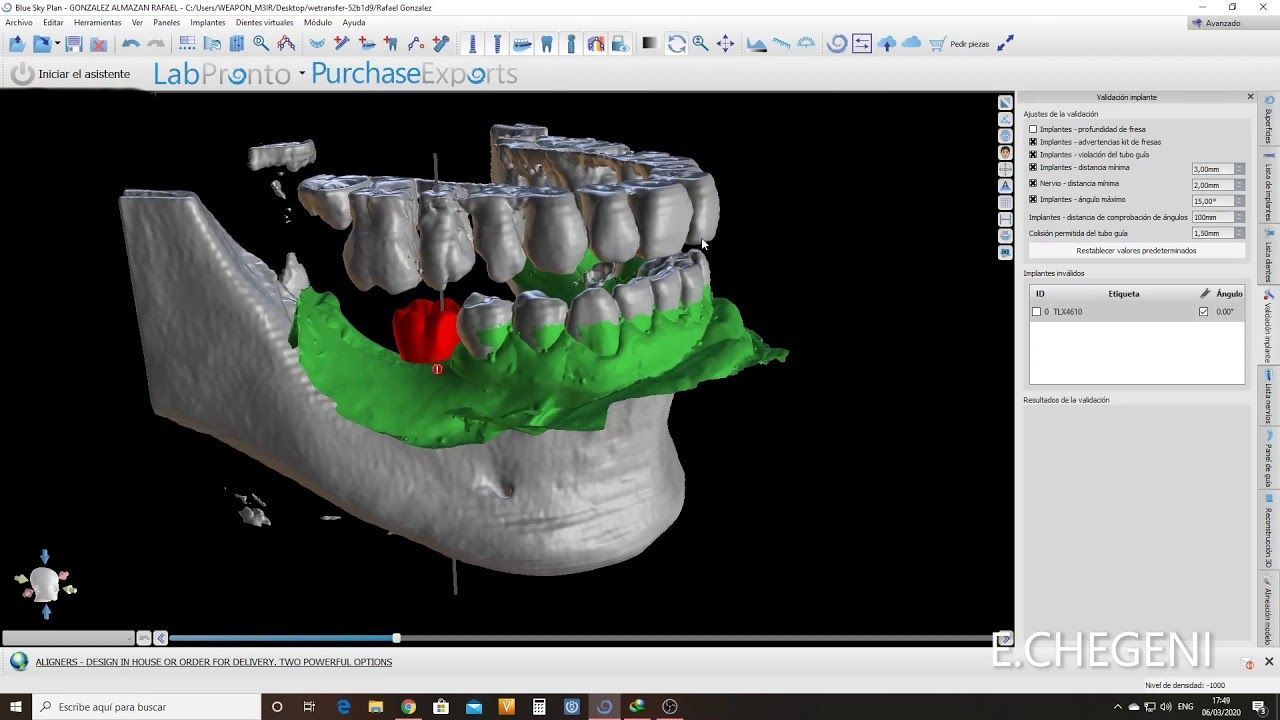

Grupo DSD es el referente nacional

En soluciones y materiales odontológicos innovadores, con tecnología avanzada para diagnósticos dentales de alta calidad.

En DSD, nos enorgullece ofrecer las mejores marcas de insumos odontológicos para tratamientos de ortodoncia, endodoncia y rehabilitación oral, implantología, y periodoncia. Con una trayectoria sólida y el respaldo de profesionales reconocidos, nuestros productos aseguran calidad y eficacia en cada procedimiento. Sabemos que la salud bucal de tus pacientes es prioritaria, y por eso elegimos solo lo mejor para ti.